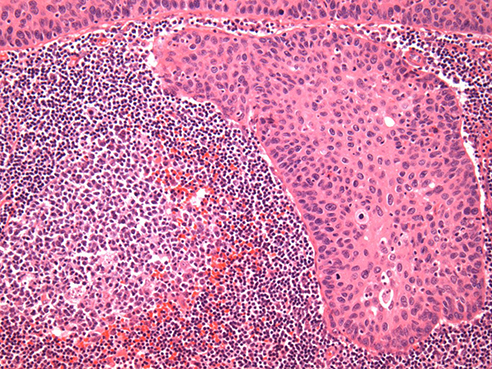

This photo shows squamous cell carcinoma of the cervix, the most common form of cervical cancer (NewYork-Presbyterian/Columbia University Irving Medical Center)